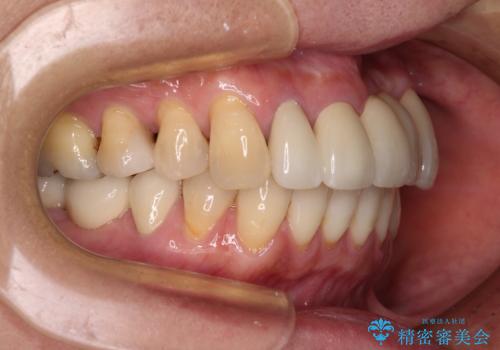

前歯のみならず、奥歯の銀歯や下顎前歯のデコボコなど、色々と気になる部分を治したいとのことでした。

前歯は抜歯が必要であったので、抜歯を行い、その後歯肉移植をおこなった上でオールセラミックブリッジによる補綴治療を行うこととしました。

下顎と上顎臼歯部については矯正治療を行い、奥歯の欠損部位はオールセラミックブリッジを、その他の銀歯はセラミックインレーなどにより治療を行うこととしました。

気になっている部分を全て治療したことで、費用はかかりましたが、仕上がりには大変満足していただき、治療をおこなって良かったと仰っていただきました。